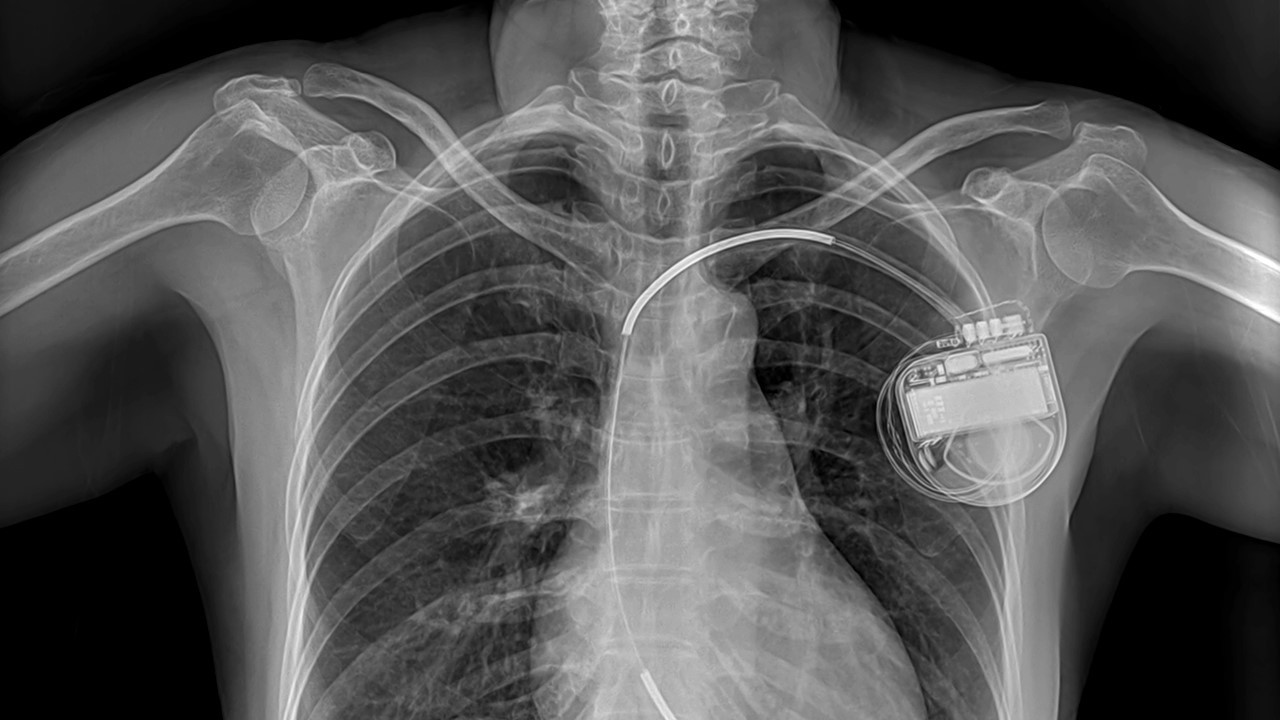

Пациента укладывают на операционный стол на спину с валиком под головой и под спиной на уровне подмышек. После обработки операционного поля хирург выполняет катетеризацию подключичной вены (левшам – справа, правшам – слева) и по специальному проводнику (струне) с использованием расширителя (интродьюсера) подводит электрод/электроды в одну из правых камер сердца (в зависимости от типа нарушения сердечного ритма). Затем хирург устанавливает необходимый порог электрического импульса, создаваемого АДК, и фиксирует проводник в сердце.

Установка проводника проводится под рентген-контролем (рентгеноскопия). После того, как проводник были установлены их прикрепляют к АДК, который помещают через небольшой разрез в левой или правой подключичной области под, в толщу большой грудной мышцы либо под ее фасцию. Затем еще раз контролируют работу аппарата и ушивают рану.